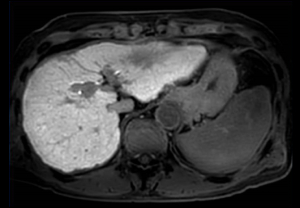

T2w TSE

Ingenia Ambition 1.5T